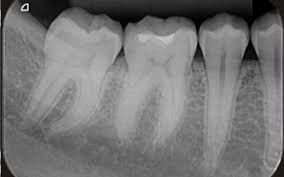

Periapical x-rays.

A periapical x-ray shows entire tooth starting from the crown to the root tip. It help your dentist to diagnose tooth decay, gum disease, bone loss or any other abnormalities in your tooth and surrounding Bone and tissues.